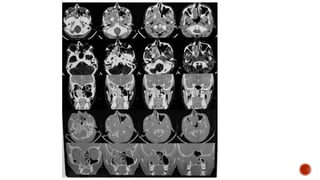

 AP and lateral radiographs of the skull show multiple tiny lucent areas with areas of

sclerosis in between, giving rise to salt and pepper skull appearance.

 Radiographs of both the legs, knees and left humerus show diffuse osteoporosis with

few well defined lytic areas.

 Radiograph of the hand shows osteoporosis with coarse trabeculations of the

phalanges with mild erosions along tteh radial aspect.

FINDINGS

 Osteopenia

 Subperiosteal resorption: classically along radial aspects of phalanges

 Floating tooth

 Subchondral resorption (lateral end of clavicles, pubic symphysis, sacroiliac joints)

 Subligamentous resorption(ischial tuberosity, trochanters)

 Brown tumors(more common in primary)

 Salt and pepper skull

 Rugger jersey spine

 Secondary and tertiary hyperparathyroidism may be associated with osteosclerosis of

renal osteodystrophy and osteomalacia of vitamin D deficiency

 Superior and inferior rib notching may be seen